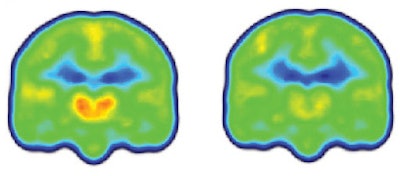

PET/MRI revealed glial activation through C-11 PBR28 binding and significantly higher levels of the translocator protein in the thalamus and other brain regions in patients with chronic lower back pain versus the control subjects.

The distinction was so consistent across the subjects that the researchers could differentiate between the two groups simply by looking at the individual images, before a statistical analysis was performed.